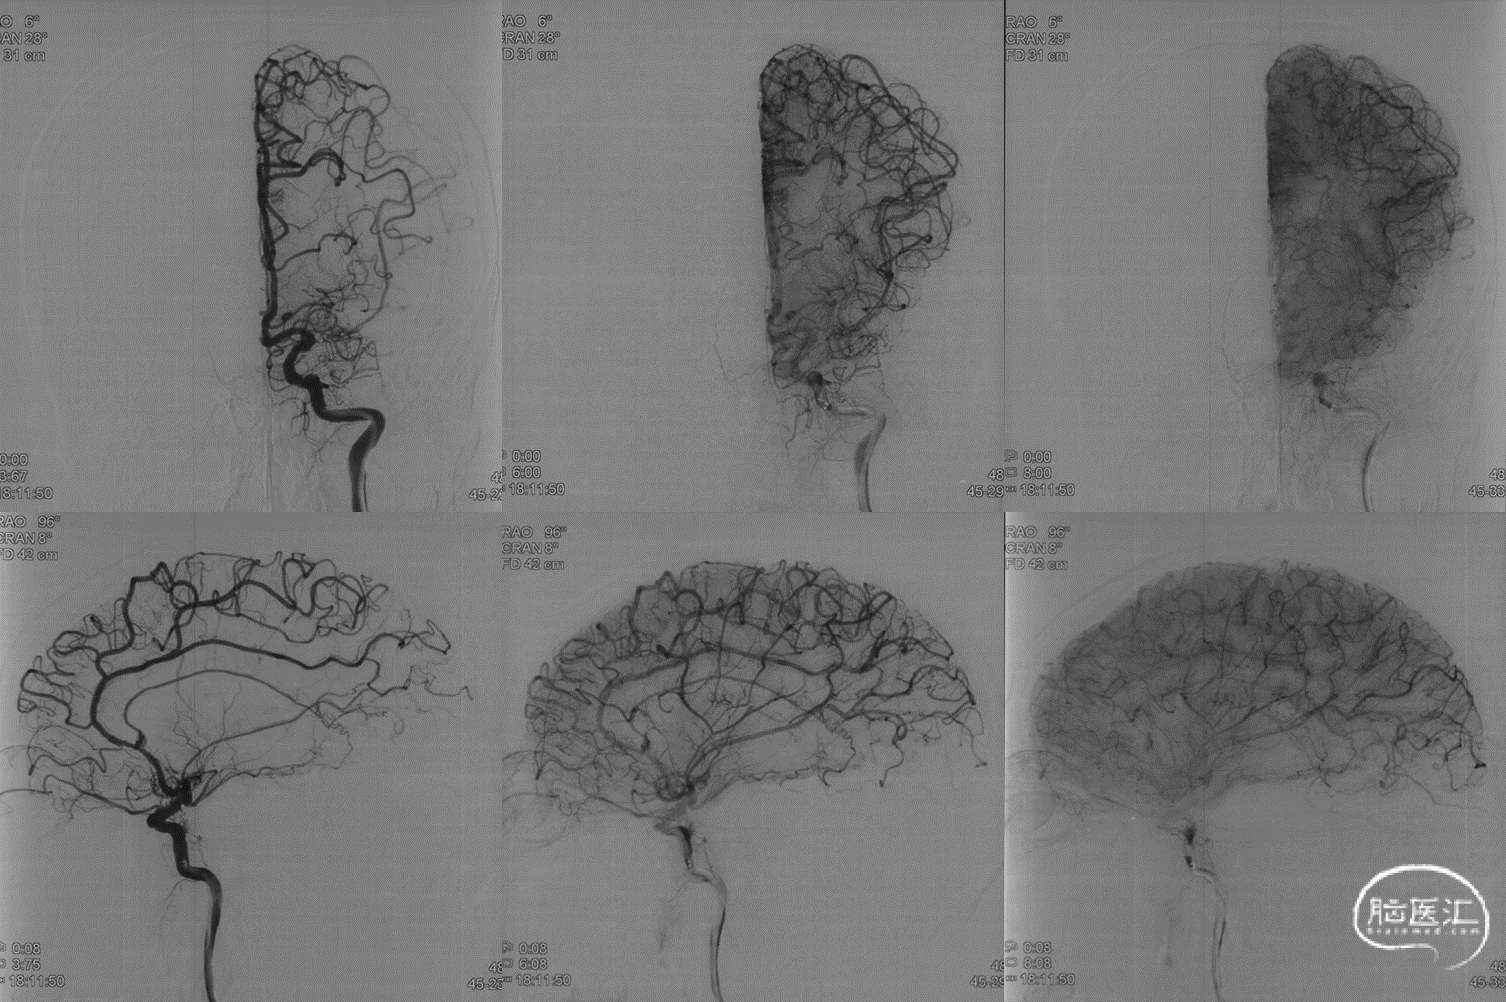

远端小血管动脉瘤是介入治疗的难点。由于远端血管细小,分支众多且大多是有功能的血管,介入栓塞动脉瘤一方面需要致密栓塞动脉瘤提高远期疗效,另一方面需要完全保留有功能的分支血管。如载瘤动脉合并狭窄,将进一步增加手术的难度和潜在的手术并发症。

本例患者是左侧大脑前动脉A2段动脉瘤,形态不规则,合并载瘤动脉狭窄,采用血流导向装置植入治疗后获得较好的影像学结果。